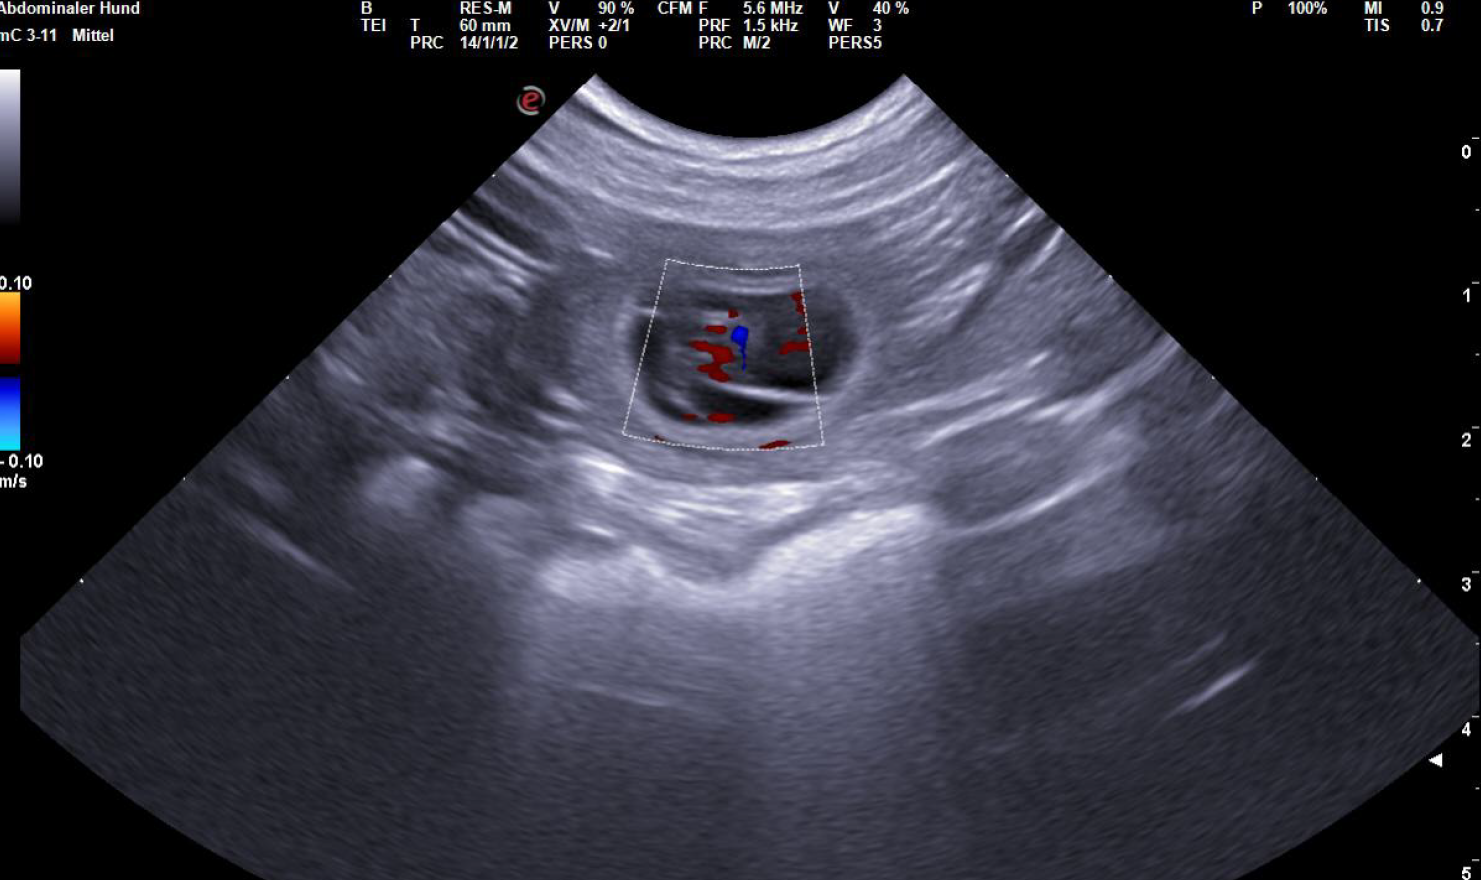

| 24 | 16,3 | 50 | Zervix Schleim sichtbar / Ultraschall bestätigt Trächtigkeit | "Die Augen und die Nervenstränge im Rückenmark werden gebildet. |

| 26 | "24-28. Tag Dies ist der beste Zeitpunkt, um die Trächtigkeit anhand des Herzschlags zu diagnostizieren. | |||

| 27 | Die Embroynen sind etwas walnussgroß und sind gleichmäßig im Uterus verteilt." | |||